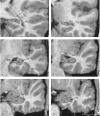

Figure 3.

Series of coronal images arranged from caudal (a) to rostral (f), indicating boundaries of the hippocampus. A, amygdala; EC, entorhinal cortex; F, fornix; H, hippocampus; LV, Lateral ventricle; MS, medial surface of the brain; RSC, retrosplenial cortex; SAS, semiannular sulcus; T, pulvinar of the thalamus; TLV, temporal horn of the lateral ventricle.